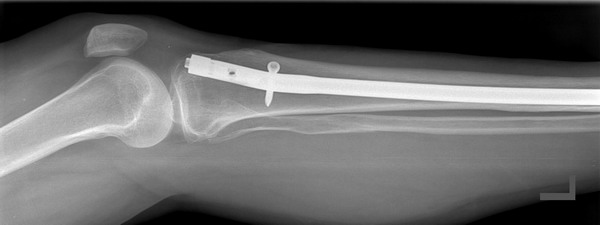

Nun können die Instrumente falls notwendig vorerst an Leichen getestet werden um eventuell verbesserungswürdiges noch zu erkennen, einfaches Instrumentarium kann direkt im OP angewandt werden. Ein gutes Beispiel für solch eine Entwicklung ist unser Universal Marknagel Extraktor. Dieses Produkt wurde zusammen mit Herrn Dr. Ferber entwickelt. |